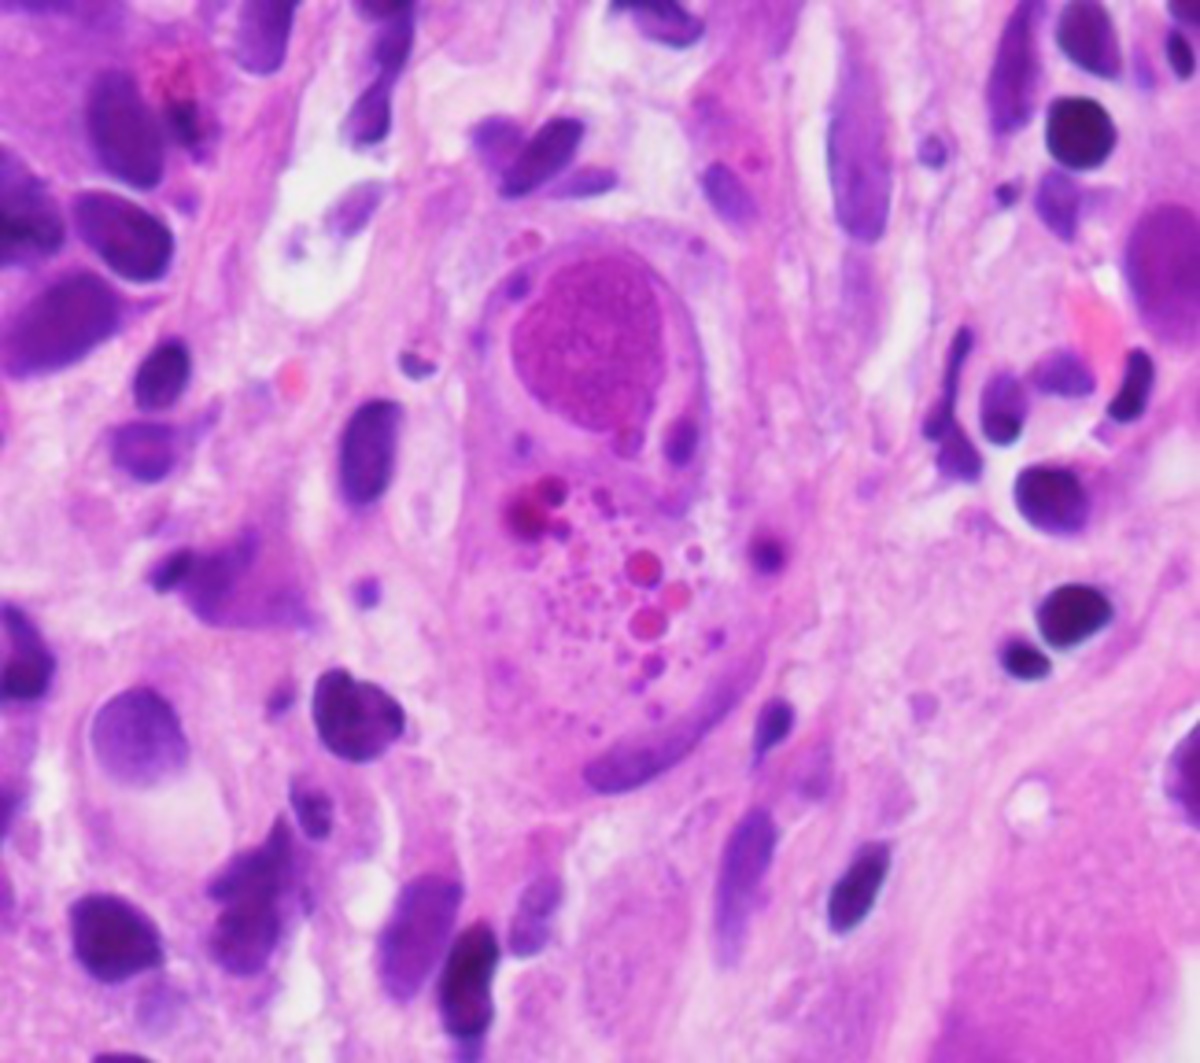

48m 1 wk diarrhea with 10-15 BM/day + intermittent, diffuse abdominal pain and denies fevers. pmh kidney transplant 6 months prior hx dm1. His immunosuppression consists of tacrolimus and mycophenolic acid. No abx, travel, or sickC. CT scan reveals right colonic wall thickening centered at the hepatic flexure with surrounding mesenteric stranding. Colonoscopy scattered erosions with surrounding erythema and edema [figure A] worse in the proximal colon. TI normal. Colon biopsies active inflammation with abnormalities in the lamina propria [figure B]. pathogen?

A

• colitis-associated with intracytoplasmic inclusions, as seen in the second image, is characteristic of cytomegalovirus (CMV) infection.